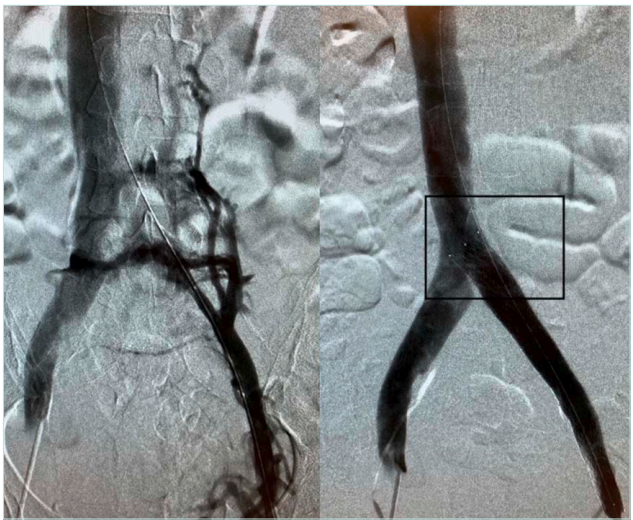

Crash resistance, defined as the stent’s capacity to ensure unidirectional external compression—particularly from overlying arterial structures or musculoskeletal motion—is a pivotal factor in long-term patency. Stents with larger nominal diameters typically exhibit superior crash resistance, retaining shape and function even under substantial mechanical load (Figure 3).24

Figure 3. Venography showing pre (left panel) and post (right panel) recanalization of a May Thurner syndrome patient with a long stent anchored to the origin of the common iliac vein.